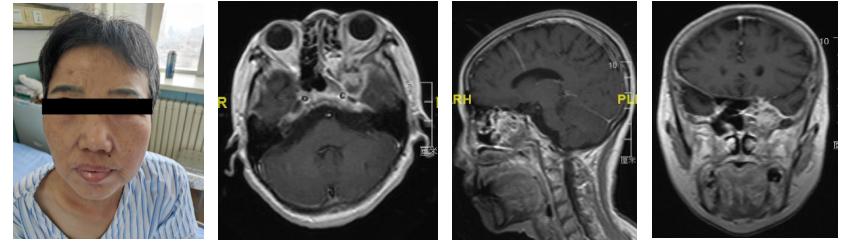

患者于2年前突发头面部的电击样疼痛,给她带来了极大的痛苦,患者及家属多地求医问药不能确诊,曾就诊于外院行伽玛刀治疗,但是术后疼痛仍不缓解,而且出现头晕、呕吐等症状,随后又进行神经阻断治疗,术后面部疼痛稍缓解,但是又出现面部的感觉障碍,额纹消失等症状,最后经多方打听慕名就诊于我院神经外科二病房王宁教授。

患者如期入院,在王宁教授的带领下,邵奇主治医师,房宇龙住院医生协助患者顺利完成了术前相关检查及会诊,确诊为颅内外沟通型占位性病变,为患者找到了真正的病因。

该患者发病时间较长,病变涉及范围广泛,浸润的结构较多,累及海绵窦、蝶窦、筛窦、上颌窦及翼腭窝,周围毗邻重要的血管及神经包括斜坡旁、海绵窦段颈内动脉、III- V颅神经、翼腭神经节及颌内动脉,手术难度大,稍有不慎将造成无法挽回的后果。

术前神经外科王宁教授团队与耳鼻喉科李慧军教授团队一同制定了周密的手术计划,手术如期顺利进行,先由耳鼻喉科王启威副主任医师内镜下行筛窦、上颌窦开放,并切除侵及相关区域病变。然后神经外科王宁教授及邵奇主治医生内镜下进行了侵及翼腭窝、蝶窦、海绵窦病变的切除。术后进行磁共振检查显示肿瘤全切,困扰折磨患者已久的典型三叉神经痛症状消失,恢复满意出院。